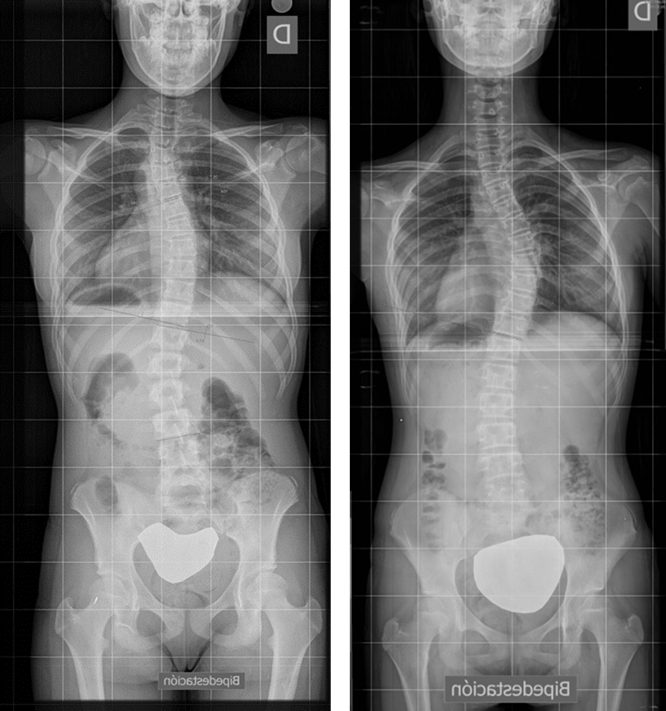

La escoliosis puede presentar una o varias curvas y en su evolución, no mejora (Figura 8). Por eso, se hace imprescindible su seguimiento con sucesivas telerradiografías, lo cual obliga, éticamente, a optimizar su estudio8.

Figura 8. Telerradiografía de escoliosis de una paciente a lo largo del tiempo. Mostrar/ocultar

Todo esto explica la repercusión estética (signo de Adams) y pulmonar de la escoliosis. Y esto nada más, define una escoliosis. En la Figura 11 se puede observar una grave escoliosis con una perfecta simetría en los hombros, pelvis y caderas.

Figura 11. Simetría en los hombros pelvis y caderas con una grave escoliosis dorsal. Mostrar/ocultar